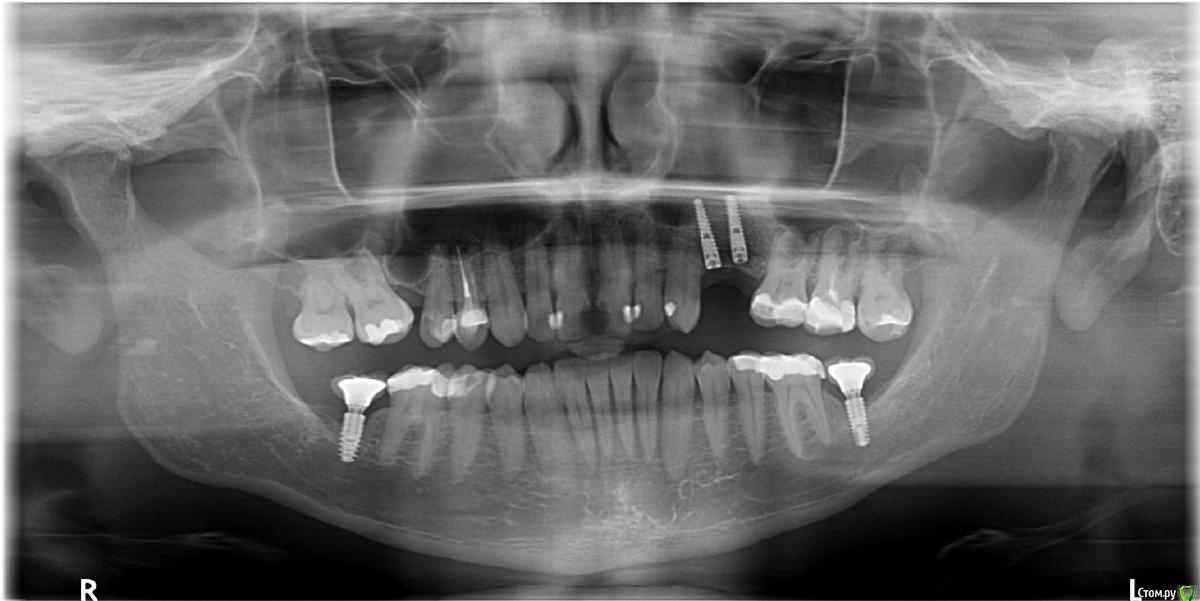

tonkin Опубликовано 9 января, 2017 Поделиться Опубликовано 9 января, 2017 Помогите определиться с числом имплантов. Отсутствуют 2 верхних зуба (в красном квадрате на пано). Расстояние между корнями ~ 16.5 мм. Вопрос следующий, какой вариант лучше (оба после планируемого синус лифтинга): 1) поставить 1 толстый имплант по центру с двойной коронкой, чтобы изобразить 2 зуба под улыбку. Тут смущает то, что в прошлом году уже такой вариант делали. Имплант расшатался за 3 месяца, и выпал (снимок импланта был сделан за 2 месяца до паноромного, где импланта уже нет). Вероятно, что имплант был коротковат для такой нагрузки (да и кости мало), и если сделать лучше, то будет держать двойную коронку нормально. 2) второй вариант - 2 тонких импланта с индивидуальными коронками, но места маловато (4 мм + 3 мм + 4 мм + 3 мм + 4 мм = 18 мм < 16.5 ). То есть все очень впритык. Смущает значительная добавочная стоимость, но с другой стороны, шатающегося импланта как в первом случае уж очень хочеться избежать. Мнения? И если стоимость - не вопрос, то будут ли 2 импланта лучше 1-го ? Дополнительный вопрос - как выглядят 2 нижних импланта на предмет качеста кости. Имплантам - 13 месяцев, коронкам - 7. Эти вроде пока держатся (тфу-тфу). Заранее благодарю за консультацию! Ссылка на комментарий

tonkin Опубликовано 1 июня, 2018 Автор Поделиться Опубликовано 1 июня, 2018 Обновление. Сделали мне дебелый синус лифтинг, кость наросла глубоко в синус. Гонял я туда-сюда, от имплантолога до протезиста. Оба мялись 1-2, непонятно. Но я, вспоминая ужасы консоли, которая раскручивала как монтировка 1 имплант, не хотел 1. В итоге протезист сделал шаблон, имплантолог загнал туда 2 импланта диаметром по 3.2 мм вроде и хорошей длины, в шахматном расположении, что бы увеличить расстояние между имплантами. Один из имплантов торчал немного не вертикально, в итоге протезист 3 раза делал слепок зубов, чтобы с лабой склепать 2 отдельные коронки. Но в конце концов вроде сделали. Потом он эти коронки долго и нудно подтачивал, и подварил немного материала чтобы между коронками улучшить контакт. В общем таки их приклеели, посмотрим теперь, как они будут держаться, и как обростут десной. Ссылка на комментарий

tonkin Опубликовано 5 июня, 2018 Автор Поделиться Опубликовано 5 июня, 2018 Пока такой, проверю, есть ли снимок с глубиной имплантов Ссылка на комментарий

tonkin Опубликовано 6 июня, 2018 Автор Поделиться Опубликовано 6 июня, 2018 Вот еще 2 пано, с наращенной костью до имплантов, и после, когда уже все зажило. Ссылка на комментарий

dok1 Опубликовано 6 июня, 2018 Поделиться Опубликовано 6 июня, 2018 Надо бы срез кт ближнего импланта с клыком. Близковато кажется. А так ничего вроде. Всё по уровню. Ссылка на комментарий

Bier Опубликовано 6 июня, 2018 Поделиться Опубликовано 6 июня, 2018 думаю, что там все ок 1 Ссылка на комментарий